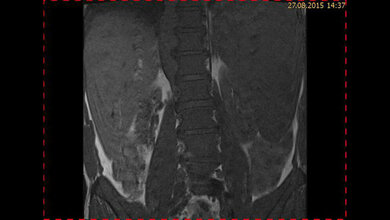

Zur Behandlung der NHL wird in der Regel eine Chemotherapie eingesetzt. In einigen Fällen ist eine Stammzelltransplantation notwendig. „Zur Beurteilung des Ansprechens wollen wir noch mehr auf die für die betroffenen Kinder und Jugendlichen weniger belastenden radiologischen Untersuchungen setzen“, sagt Professorin Renz. Dafür müsse aber zunächst eine Methode entwickelt werden, um die Flut an Informationen aus den radiologischen Bildern wie Computertomografie (CT) und Magnetresonanztomografie (MRT) so herauszufiltern und aufzubereiten, dass sie einem bestimmten Lymphom-Stadium eindeutiger zuzuordnen sind.

„Bislang erfolgt die Bestimmung mittels CT und MRT keinem Referenzstandard, an dem sich die Radiologinnen und Radiologen orientieren können“, erklärt die Projektleiterin. „So bleibt eine Vielzahl möglicher verfügbarer Hinweise auf das Tumorstadium und das Rückfallrisiko leider ungenutzt.“ Ein wesentliches Ziel von RACOON-RESCUE sei es daher, eine standardisierte und automatisierte Bildanalyse zu entwickeln. Das Vorhaben soll sich dabei nicht nur auf die radiologischen Bilddaten, die im Rahmen der klinischen Routine bereits erfasst wurden, stützen. Die Forschenden wollen auch das „NHL-Berlin-Frankfurt-Münster-Register“ nutzen, das seit 2012 klinische Daten von Kindern und Jugendlichen aller NHL-Untergruppen in Deutschland erhebt.

„Wir erhalten so einen neuen und einzigartigen Datensatz, den wir mit Hilfe künstlicher Intelligenz automatisiert auswerten wollen, um die Vorhersagen über den Therapieerfolg zu verbessern und das individuelle Rückfallrisiko vorherzusagen“, erklärt Professor Renz. Auch bildbasierte Merkmale, wie etwa Größe, Art und Form der Lymphknoten sollen einbezogen werden und mithelfen, das maschinelle Vorhersagemodell zu trainieren. „Am Ende wollen wir daraus eine digitale Befundungsmaske entwickeln,um das jeweilige Tumorstadium aus den CT- und MRT-Bildern direkt zu bestimmen, das Therapieansprechen zu beurteilen und dadurch auch die Tumornachsorge zu verbessern.“ Die automatisierte Bildauswertung soll zukünftig erlauben, die radiologische Diagnostik umfassender zu nutzen, den Einsatz invasiver Untersuchungen wie Gewebe- oder Flüssigkeitsentnahmen zu verringern und bisher unklare Befunde besser einzuordnen. „Dadurch wird es auch möglich herausfinden, welche Patientinnen und Patienten nach einer Therapie ein hohes Rückfallrisiko haben und das Therapiekonzept kann individueller angepasst werden.“